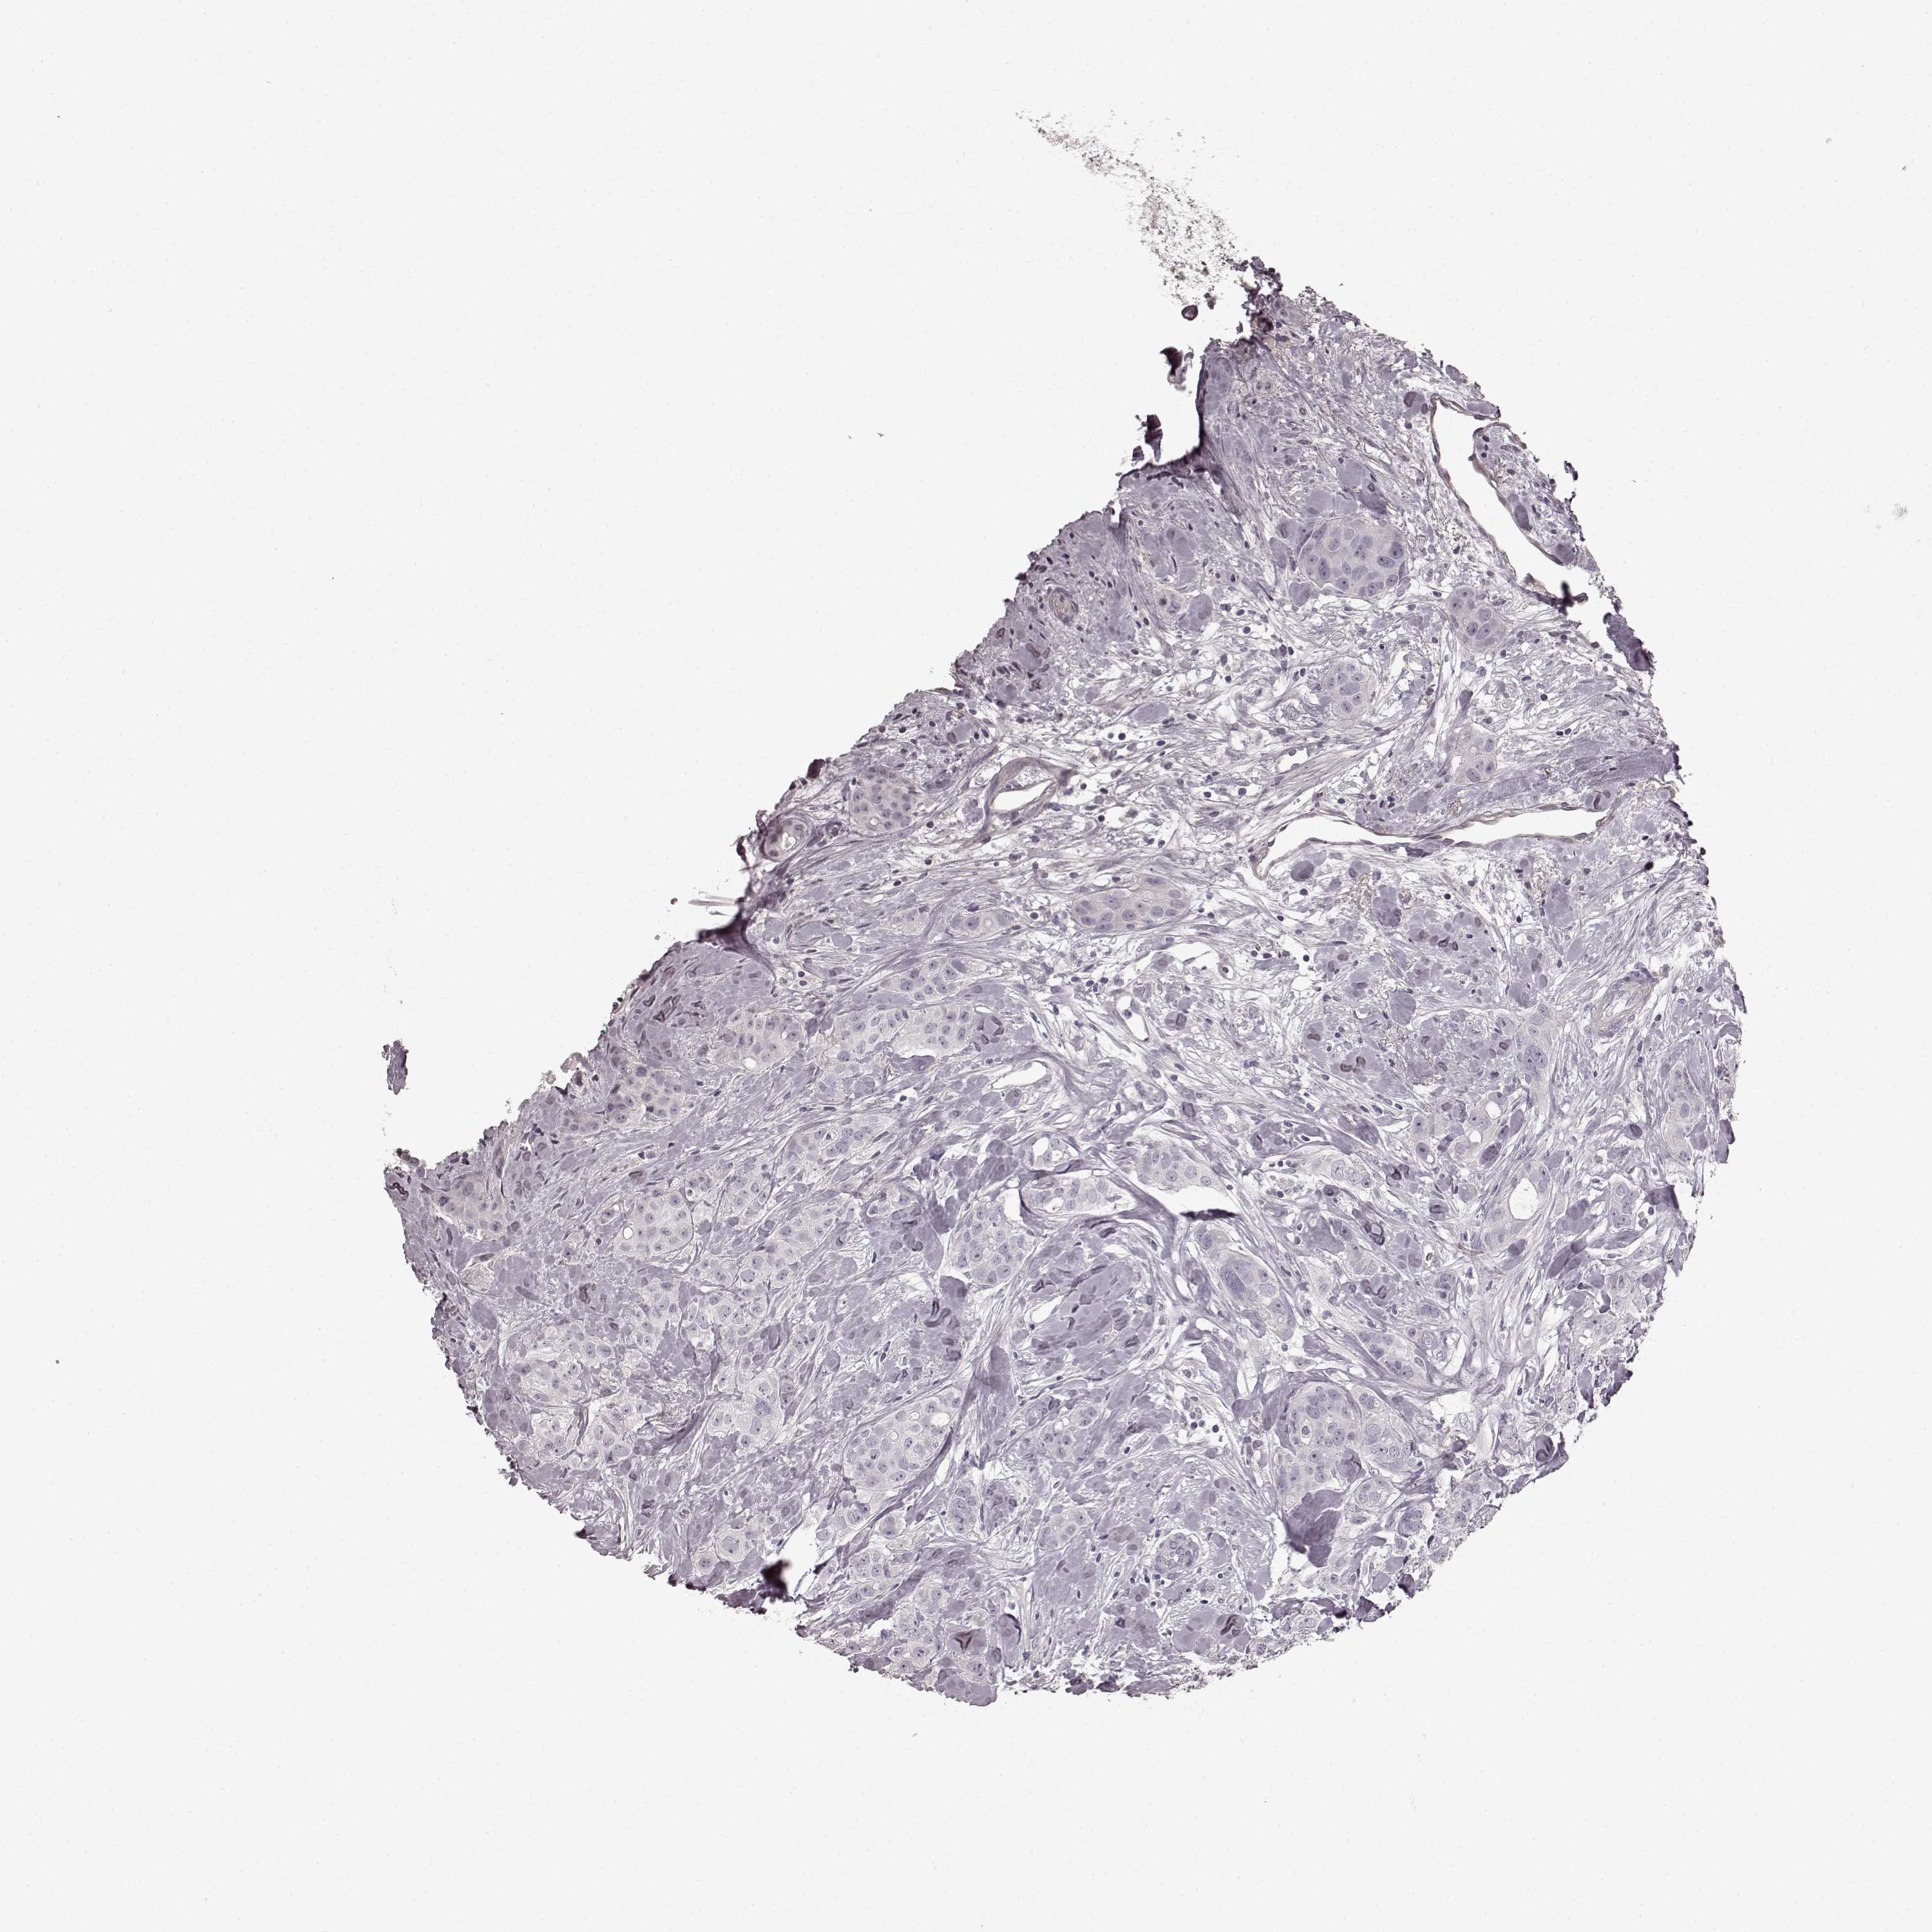

CANCER BREAST CANCER Show tissue menu

BRCA TCGA BRCA VALIDATION PROTEIN EXPRESSION